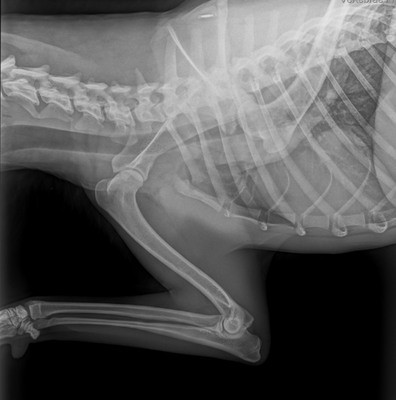

Hip & Elbow x-rays

Perhaps one of the most well known health testing in dogs, hip and elbow x-rays taken to check for signs of dysplasia. Once taken by a qualified vet the x-rays are then sent to a scoring board dependent on country of residence or personal choice of the breeder. To the right, is a comparison of the results across the most common available testing organisations.

The organisation which we primarily use for our program is BVA.

Elbows: Elbows are graded individually with a score from 0-3 on each side. The ideal being a score of 0. To have an elbow scored there must be at least two x-rays; flexed lateral and neutral view. Elbow dysplasia is uncommon in both Komondor and Mudi.

Hips: Under the BVA scheme, the marking of hips is broken down into 9 sections, the maximum marks in any one section is 6, and the maximum overall is 106. The aim is to obtain the combined lowest number possible, the best result possible being a 0. Please view the example images of our dogs results attached above to see the 9 possible sections.